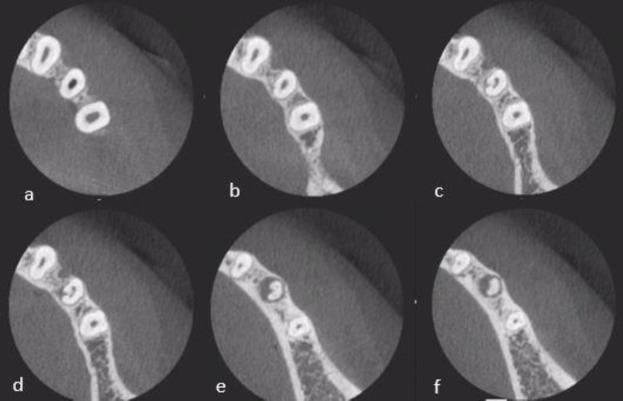

Our article aimed to present a curious case of a mandibular premolar with a C-shaped root canal and to review the available literature on this anatomical variation. Mandibular premolar teeth account for the greatest endodontic challenges in the course of treatment on account of the morphological variations in their root canal systems, including extra root(s)/canal(s) or a C-shaped configuration. A 20-year-old female patient was referred to the Department of Endodontics of Mashhad Faculty of Dentistry, suffering from abscess, and pain while chewing. On examination the culprit was found to be the left mandibular first premolar. Following special tests and periapical radiography, we found an amalgam restoration proximate to the non-vital pulp chamber, as well as an unusually complex root canal anatomy with periapical radiolucency. A non-surgical root canal treatment with the aid of a dental operating microscope was considered as the treatment plan. Clinicians should always anticipate the presence of a C-shaped configuration in mandibular premolars, and make use of all the available tools to locate and treat such cases. A substantial knowledge of root canal anatomy would be prudent to ensure a successful outcome ensuing surgical and non-surgical root canal treatments.

我们的文章旨在呈现一例具有C形根管的下颌前磨牙的罕见病例,并回顾有关这种解剖变异的现有文献。由于下颌前磨牙根管系统存在形态变异,包括额外的根/根管或C形结构,因此在治疗过程中,它们是牙髓治疗面临的最大挑战。一名20岁女性患者因脓肿和咀嚼时疼痛被转诊至马什哈德牙科学院牙髓病科。检查发现罪魁祸首是左下颌第一前磨牙。经过特殊检查和根尖周X线片检查,我们发现靠近无活力牙髓腔处有银汞合金修复体,以及异常复杂的根管解剖结构和根尖周透射区。治疗方案考虑在牙科手术显微镜辅助下进行非手术根管治疗。临床医生应始终预期下颌前磨牙存在C形结构,并利用所有可用工具来定位和治疗此类病例。为确保手术和非手术根管治疗取得成功结果,对根管解剖有充分了解是明智的。